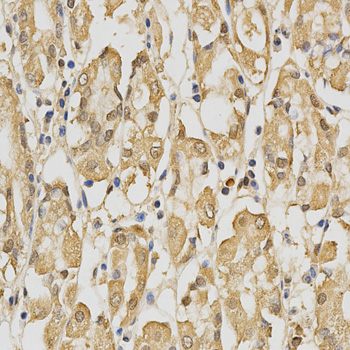

Immunohistochemistry of paraffin-embedded human kidney cancer using PRDX4 antibody at dilution of 1:200 (x400 lens)